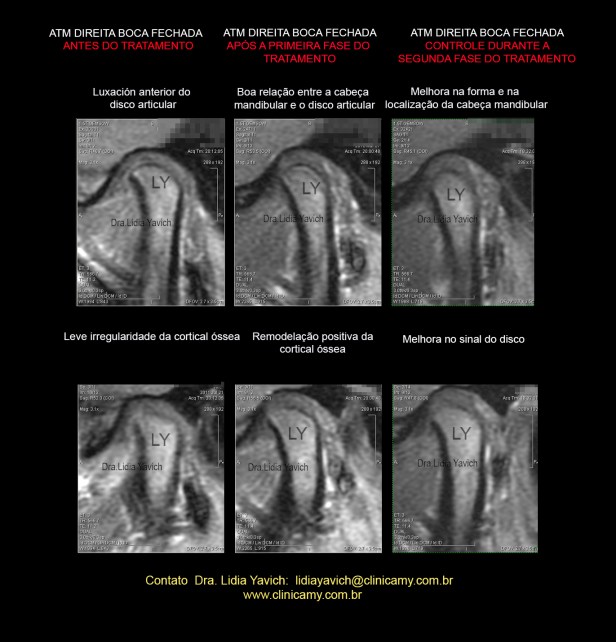

42 RNM AFTER TREATMENT

Comparação dos cortes sagitais da RNM da ATM direita boca fechada antes e após a primeira fase do tratamento.

Observar a boa relação entre a cabeça mandibular e o disco articular.

Observar a remodelação positiva da cortical óssea.

Comparação dos cortes sagitais da RNM da ATM direita boca fechada , após a primeira fase do tratamento e no controle da segunda fase do tratamento ainda não concluído.

Nesta imagem temos uma terceira RNM que não foi apresentada no Congresso da IAO.

As estruturas continuam melhorando.